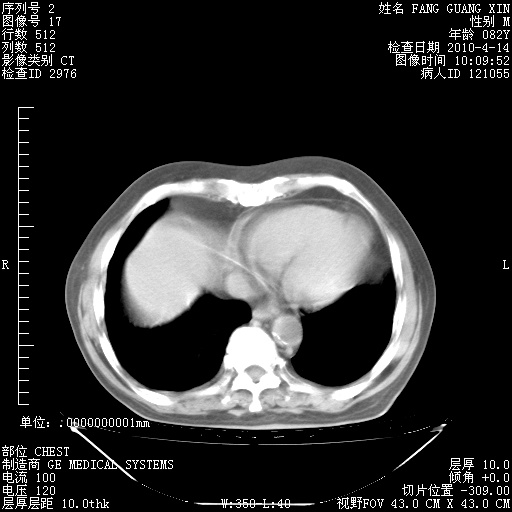

4月14日肺部CT

4月28日肺部CT——再次出现类似去年5月9日——透光度降低,(影像科认为)“间质性”改变。